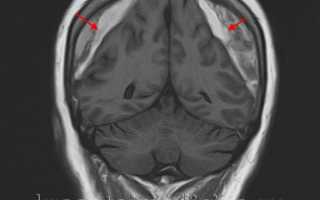

МРТ головного мозга. Массивная двухсторонняя хроническая субдуральная гематома.

Ключевыми методами диагностики субдуральной гематомы являются КТ и МРТ головного мозга. Для острых гематом предпочтительнее КТ, которая показывает однородную зону повышенной плотности серповидной формы. Со временем гематома разуплотняется, и через 1-6 недель она перестает отличаться по плотности от окружающих тканей. В таких случаях диагноз основывается на смещении латеральных отделов мозга в медиальном направлении и признаках сдавления бокового желудочка.

При МРТ может наблюдаться пониженная контрастность зоны острой гематомы, тогда как хронические субдуральные гематомы обычно имеют гиперинтенсивность в Т2 режиме. В сложных случаях помогает МРТ с контрастированием: интенсивное накопление контраста капсулой гематомы позволяет дифференцировать ее от арахноидальной кисты или субдуральной гигромы.